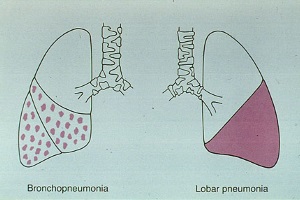

Підвищення температури тіла (амплітуда від субфебрильних цифр до 39-40 °С); кашель на початку захворювання сухий, малопродуктивний, потім вологий

Клінична картина пневмонії, обумовленої Mycoplasma pneumoniae.

Частіше бувають у дітей першого року життя. Вони протікають більш тяжко. Полісегментарні ураження легень характерні для аденовірусної інфекції....

Для характеристики анатомічного і функціонального стану легень використовують наступні терміни: «норма», «варіант норми»,«аномалія розвитку», «вада розвитку». При ваді розвитку функціональні порушення і/або прояви хвороби вже існують або можуть виникнути.